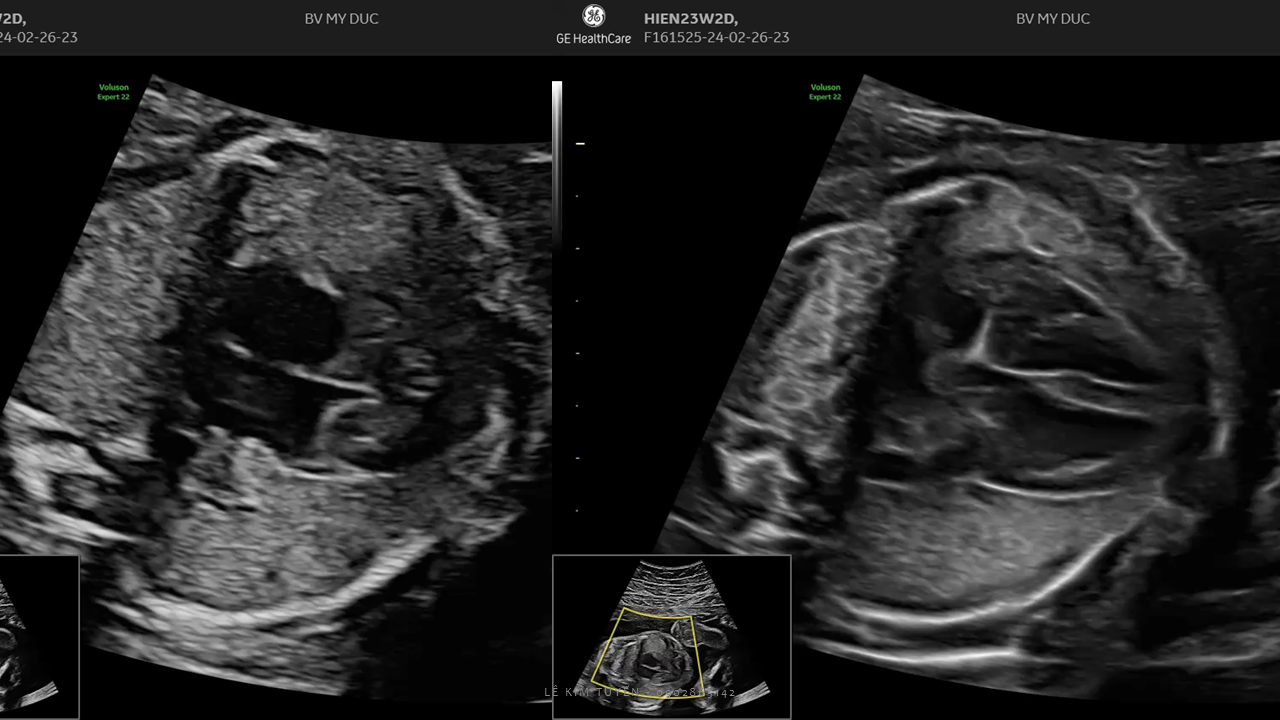

Siêu âm tim thai - Các kỹ thuật hiện đại

TS. BS. Lê Kim Tuyến

Bệnh viện Tim Tâm Đức